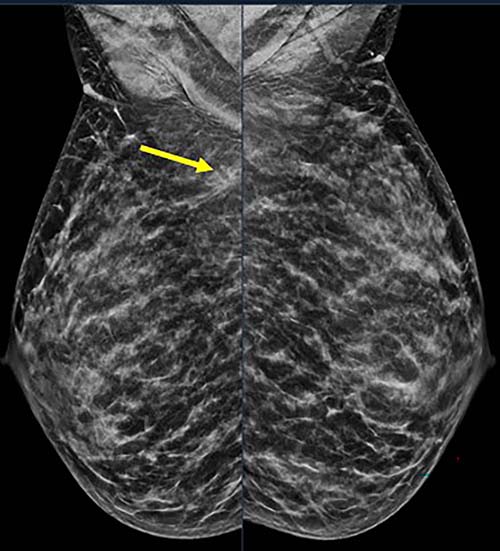

Figure 2. 40-year-old patient presents for routine screening. Family history of paternal grandmother age 55. Extremely dense breast tissue is noted on mammography right and left mediolateral oblique (side angle) view. In addition, an area of architectural distortion is seen at the posterior right breast on right view (see arrow).

Figure 3. Spot on right mediolateral oblique (side angle) view. Area of distortion persists on additional mammographic views, and a mass is identified on subsequent breast ultrasound. Ultrasound guided biopsy was performed and revealed nuclear grade 1 invasive ductal carcinoma.